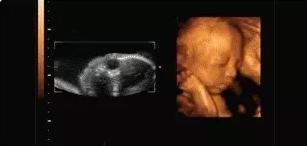

本宝宝有些困了——打哈欠

麻麻,我正在挠耳朵

本宝宝有些乏了——揉眼睛